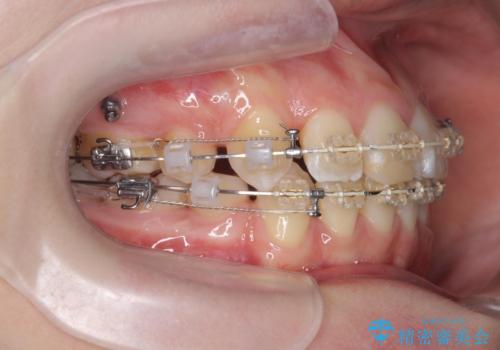

突き出た前歯を治したい 小臼歯抜歯+マルチブラケット矯正

- 矯正装置

- ワイヤー矯正

- 治療期間

- 2年8ヶ月

- 突き出て、気になる前歯の角度の改善を求めて来院されました。

前歯の角度を改善するために小臼歯4本の抜歯を行いワイヤー マルチブラケットを用いて、しっかりと前歯の角度を改善する治療計画としました。